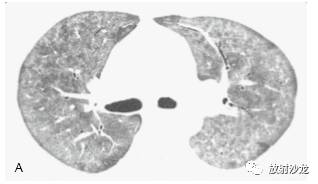

如磨玻璃影很轻微或弥漫分布,程度一致的累及全肺,则辨认困难。但磨玻璃影几乎总是呈片状分布,累及有些肺区,而不累及其他肺区。 这种肺实质的“地图样”表现很容易有信心地检 出和诊断(图5-3,图5-5)。在有些病例中,整 个肺小叶表现为异常致密,而邻近肺小叶正常。另一些病例的磨玻璃影呈小叶中心性和支气管周 围分布,形成边缘不清的小叶中心性结节。磨玻璃影可累及个别肺段和肺叶,也可累及不按肺段的肺区(图 5-6),或是弥漫的(图 5-7)。在肺区内出现表现“过黑”的含气支气管 也是有磨玻璃影的线索,这种黑色支气管表现本 质上是空气支气管征。

当考虑磨玻璃影的鉴别诊断时,重要的是要知道病例的症状是急性、亚急性还是慢性的(表 5-1)。在这些磨玻璃影原因中,呈典型急性表现 的是肺水肿;肺出血(图5-2);各种肺炎,尤其是诸如耶氏孢子菌肺炎(PJP)(图 5-3, 图 5-7,图5-10)的非典型肺炎, 病毒性肺炎(如巨细胞病毒性),支原体肺炎;急性间质性肺炎(AIP)及其他原 因的弥漫性肺泡损伤(DAD)(图 5-6)和急性 呼吸窘迫综合征(ARDS),包括慢性间质性 肺炎的急性恶化;急性嗜酸性肺炎;急性过敏性肺炎,吸入性和早期放射性肺炎。